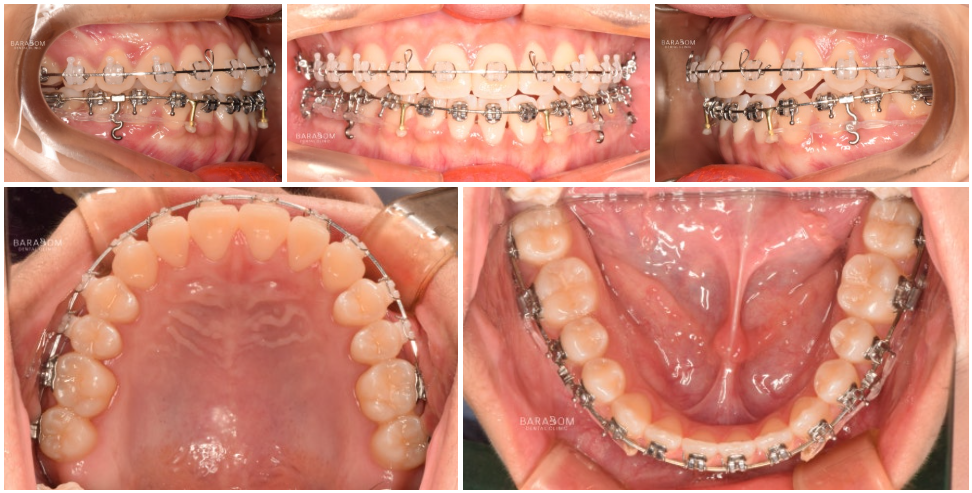

장치(브라켓)를 달고

변위된 치아를 제 자리로 이동시킴과 동시에

아랫치열을 후방으로 밀기 시작합니다.

그래야 안정적인 교합을

유도할 수 있기 때문이죠.

아랫 치열을 당기는 힘을

조절하기 위해서 스프링을 사용합니다.

✔동시에 어금니는 정출 즉,

위로 올라오도록 유도하고

아래턱은 시계방향으로 회전하여

전치부의 정상적인 맞물림을 위해

윗쪽 앞니의 정출을 유도합니다.

더불어 미니 임플란트를 활용하여

아래 치열의 후방 이동을

더욱 확실하게 유도합니다.

이와 더불어 3급 부정교합임에도 2급 고무줄을 활용하여 긍정적인 변화를 유도합니다.

고무줄의 탄성을 이용해

적절한 위치로 배열을 도모하는

방법을 사용하는 것입니다.

윗니는 뒤로 보내면서

아래 치아를 앞으로 당기며

교합을 조절하는 과정에서

탄성을 활용합니다.

어떤 위치에 걸어주느냐에 따라

유도하는 방향이 달라지는데요,

✅대개 2급 환자에게 시행되지만

이 경우 맞물림을 시계방향으로

회전하는 과정이 필요하여 적용하는 것입니다.

입술(순측)으로 경사를 이루던 앞니를

설측(혀)가 있는 쪽으로 기울어지게 유도하고,

이와 더불어 씹는면 쪽으로 정출되도록

움직임을 만들어냅니다.

이 과정은 정말 세밀한 조절이 필요합니다.